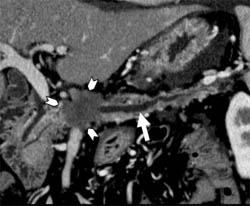

肝細胞癌と肝内胆管癌の混合症例を提示します。図1では、青矢印のやや黒く写るところが肝内胆管癌で、赤矢印の白く写るところが肝細胞癌です。造影剤注入後に早いタイミングで撮影することによって腫瘍の鑑別がしやすくなります。図2は同じ症例の3D画像です。血管構築像を3D作成することによって腫瘍と血管の位置が明確になり、手術の際に役に立ちます。図3は膵臓に沿って断面の傾きを調整した画像(多方向断面)で、膵臓中央部に腫瘍(小矢印に囲まれた部位)があり、腫瘍によって閉塞した膵管(大矢印)が拡張している様子が観察されます。